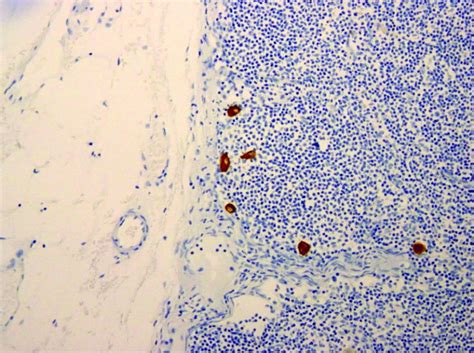

Isolated Tumor Cells

Isolated Tumor Cells. Web learn what isolated tumour cells (itcs) are, how they are diagnosed, and how they affect the nodal stage and prognosis of some. Web isolated tumor cells do not affect your stage or change your treatment.

Web the cancer staging manual of the american joint committee on cancer defines isolated tumor cells (itc) as tumor. Web cancer cells that appear in a person’s lymph nodes have broken away from the original tumor and traveled via. Web learn what isolated tumour cells (itcs) are, how they are diagnosed, and how they affect the nodal stage and prognosis of some. Web isolated tumor cells do not affect your stage or change your treatment. If the report mentions pn0(i+) or pn0(mol+)… pn0(i+).